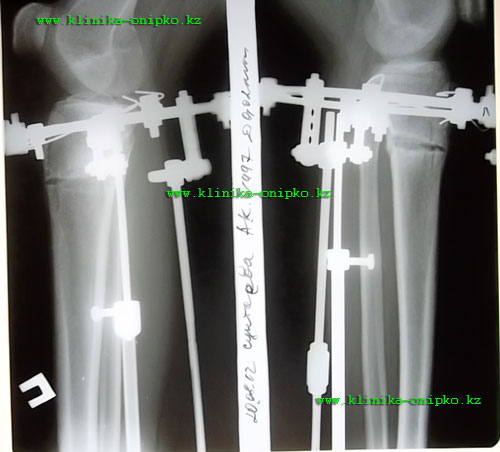

рентгеновские снимки на 11- ый день после операции. Кости выровнены, вышла на фиксацию!